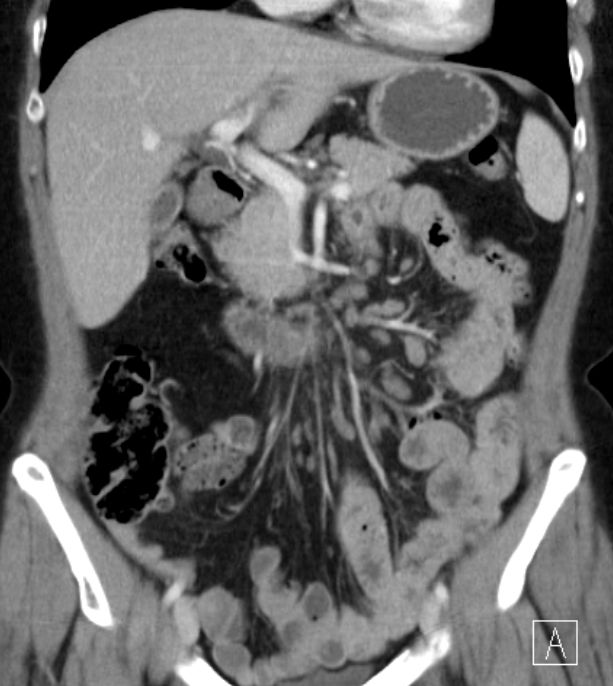

Koronares CT mit Darstellung zahlreicher

Lymphknotenmetastasen links axillär